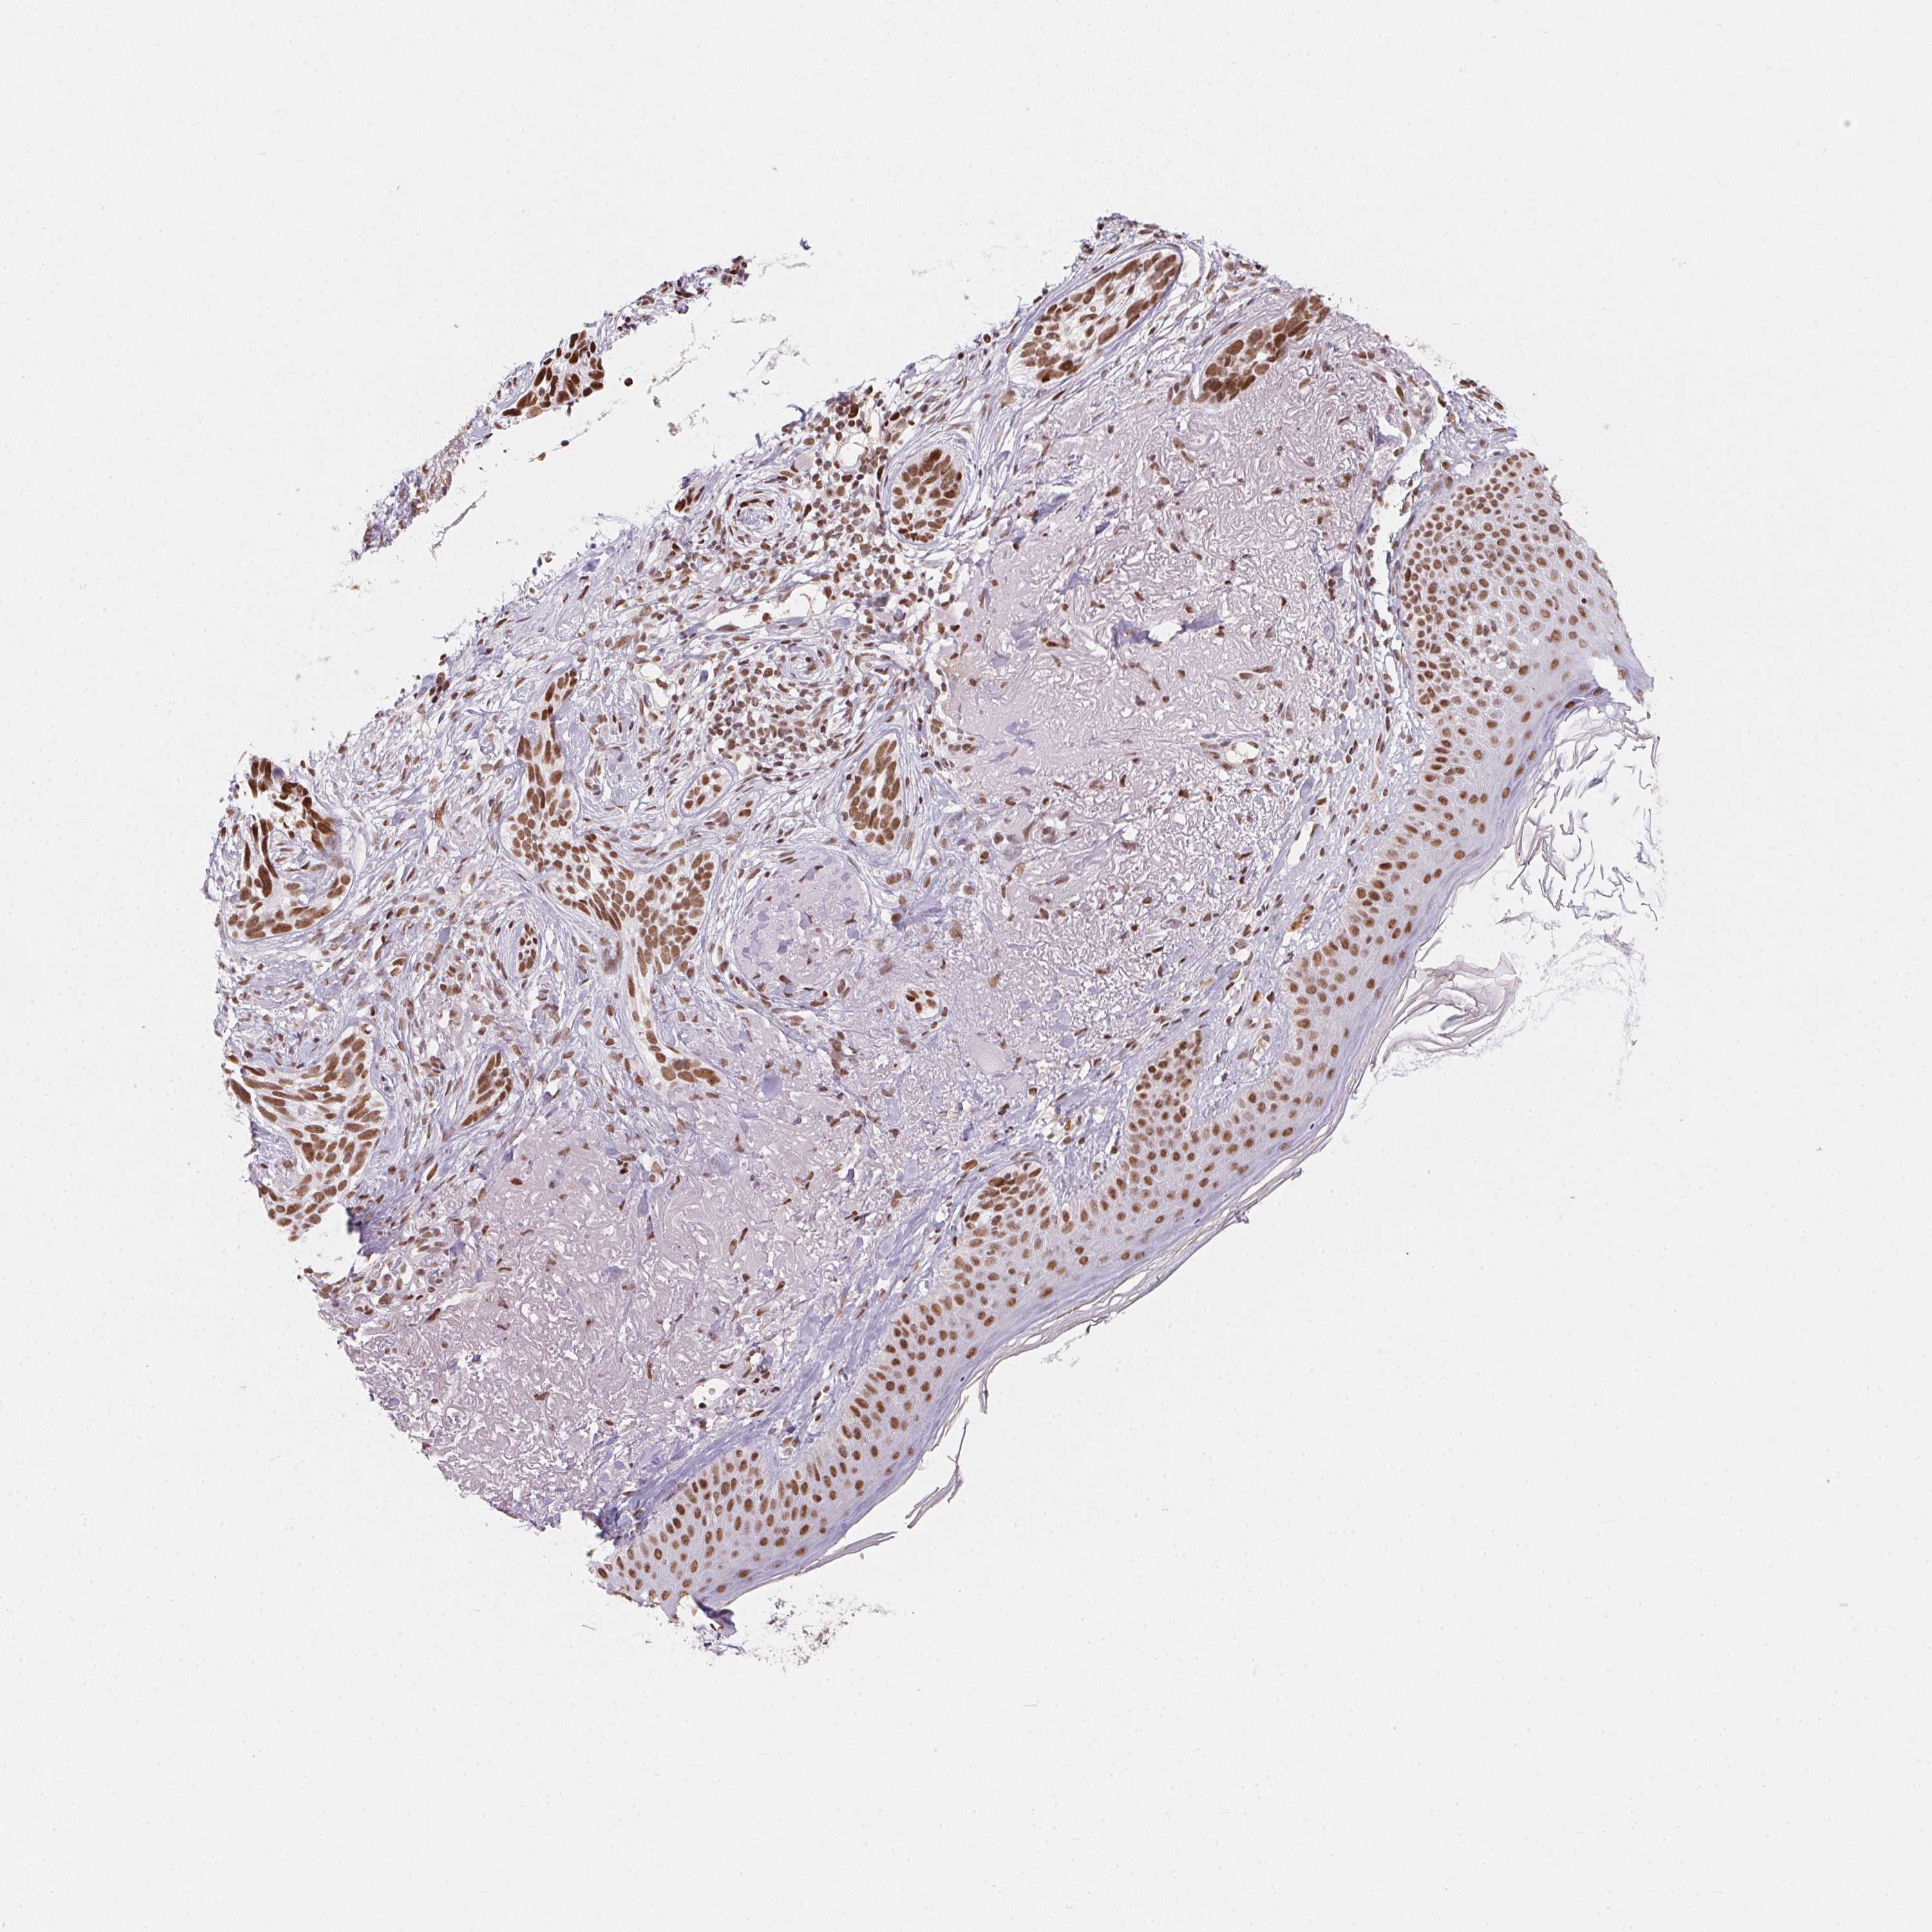

SKIN CANCER - Protein expressioni

A mouse-over function shows sample information and annotation data. Click on an image to view it in a full screen mode. Samples can be filtered based on level of antibody staining by selecting one or several of the following categories: high, medium, low and not detected. The assay and annotation is described here.

Each image is clickable and will lead to virtual microscopy that enables deeper exploration of all samples and also displays staining intensity scores, fraction scores and subcellular localization as well as patient and tissue information for each sample.

Antibody HPA064887

Staining

High

Intensity

Strong

Quantity

>75%

Location

Nuclear

Basal cell carcinoma

BCC, high aggressive